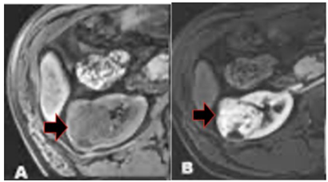

Observe o exame a seguir.

Esse exame mostra

Com relação à lesão acima, assinalada pela seta, é correto afirmar que se trata de